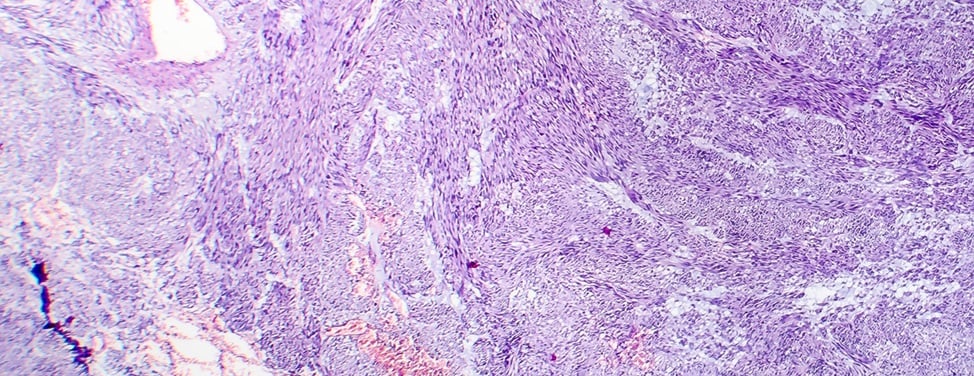

Fibroids are round growths that develop in the uterus. They are almost always benign, or non-cancerous. Fibroids range in size from as small as a pea to as large as a melon. They are also called leiomyomas or myomas.

Fibroids are very common, affecting an estimated 20 to 50 percent of all women. They are most likely to affect women in their 30s and 40s, and for reasons we don't understand, occur more frequently in African-Americans. Many women with fibroids have family members who also have them.